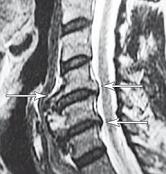

На рентгенограмме № 6 поясничного отдела позвоночника выраженный остеофитоз, спондилёз третьей степени, что также хорошо видно на МРТ № 39 поясничного отдела позвоночника МРТ № 40 ![]() МРТ № 41

На МРТ № 40 наблюдается типичный пример развития стеноза второго типа в шейном отделе позвоночника. И аналогичная картина, только, в поясничном отделе позвоночника, отображена на МРТ № 41 Стеноз Стеноз позвоночного канала встречается довольно часто, во всяком случае в моей практике. В данной книге я уже упоминал о том, что стеноз спинномозгового канала (то есть его сужение) может вызывать серьёзные осложнения при течении таких заболеваний, как например, грыжи межпозвонкового диска. Для лучшего понимания происходящих процессов давайте в общих чертах рассмотрим, что такое стеноз и чем он опасен. Итак, стеноз — это врождённое или приобретённое аномальное сужение просвета какого-либо полого органа (пищевода, кишечника, кровеносного сосуда и др.) или отверстия между полостями (например, при пороках сердца). Стеноз позвоночного канала характеризуется его патологическим сужением. Исходя из анатомо-физиологических особенностей позвоночного канала, который является вместилищем и в тоже время охранным футляром для спинного мозга, даже незначительное его сужение может оказаться фатальным для спинного мозга. К примеру, при развитии абсолютного стеноза позвоночника спинной мозг может быть компримирован (сжат) вместе с артериями. В свою очередь это неизбежно ведёт к развитию ишемии (от греч. ischo — «задерживаю, останавливаю» и haima — «кровь»; уменьшение кровоснабжения участка тела, органа или ткани вследствие ослабления или прекращения притока к нему артериальной крови) тех участков спинного мозга, где блокировано кровоснабжение сдавленными сосудами. Ещё в конце XIX века, а точнее в 1880 году, в своей работе М. Литтен отметил, что спинной мозг более чувствителен к ишемическим повреждениям и недостатку кислорода, чем другие ткани организма. А вот отечественному невропатологу, ученику В. М. Бехтерева и одному из первых нейрохирургов, Л. М. Пуссепу в 1902 году удалось в эксперименте на животных показать, что даже непродолжительная ишемия спинного мозга влечёт за собой некроз (отмирание) нервных клеток передних рогов спинного мозга. Если добавить к этому ещё и неизбежное нарушение ликвородинамики и развития (вследствие сдавления оболочек спинного мозга) эпидурита и арахноидита, то возникновение болевых, корешковых и сосудистых синдромов (в виде миелоишемии, радикулоишемии или миелорадикулоишемии) становятся вполне объяснимыми и понятными. Исходя из классификации, предложенной доктором I. Stephen, которой пользуется большинство авторов в своих работах, стеноз позвоночного канала позвоночника, как я уже упоминал, бывает двух типов. Тип первый — врождённый, или как его ещё называют идиопатический, то есть беспричинный (неизвестного, неясного происхождения). Второй тип — приобретённый, возникший вследствие дегенеративно-дистрофических процессов в позвоночнике, посттравматический или обусловленный другими причинами, которые привели к стенозированию (сужению) позвоночного канала. Например, грыжа межпозвонкового диска даже центральной локализации, имеющая размер всего 6 мм в дорсальном направлении в поясничном отделе позвоночника с сагиттальным размером спинномозгового канала в 15 мм приводит к формированию абсолютного стеноза второго типа (приобретённого) и может вызвать серьёзные осложнения. А при стенозе первого типа (врождённого, см. МРТ № 43), к примеру с сагиттальным размером спинномозгового канала в поясничном отделе 12 мм, даже трёхмиллиметровая протрузия межпозвонкового диска может привести к развитию слабости в ногах, мышечной атрофии или, как описывал данные состояния Dejerine ещё в 1911 г., «перемежающейся хромоте спинальной природы». |